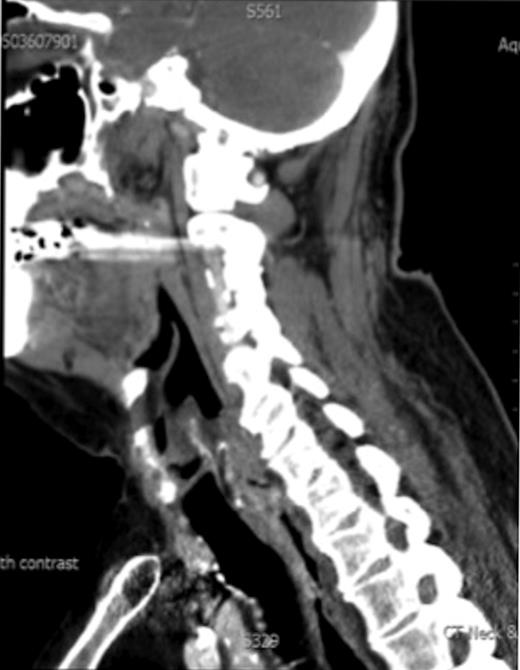

A 67-year-old man presented to our ENT department with history suggestive of globus feeling in the throat. The patient had received a full course of radiotherapy to the larynx for well-differentiated T1N0M0, squamous cell carcinoma of the larynx. There was no past history of hereditary conditions predisposing to sarcomas, including Recklinghausen's disease, hereditary forms of retinoblastoma and Wilms tumour. Direct laryngoscopic examination revealed a postcricoid tumour extending to the oesophagus. Biopsy was reported as a grade 2 spindle cell sarcoma. Computed tomographic scans demonstrated a post-cricoid lesion extending into the cervical oesophagus (Fig. 1). No cervical lymphadenopathy or distant metastases were noted.

CT scan showing the post cricoid carcinoma extending down to upper oesophagus.